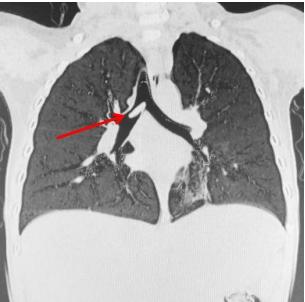

佛山市婦幼保健院在微信公眾號發文講述事件,指小周誤吞黃皮核後,家人初時覺得小周沒有甚麼異常,但後來小周日漸咳嗽、氣喘,多次看醫生都沒有明顯改善,直至去到佛山市婦幼保健院接受詳細檢查,才發現小周「氣管遠端-右主支氣管」有柱狀異物,並有「左肺肺炎」。